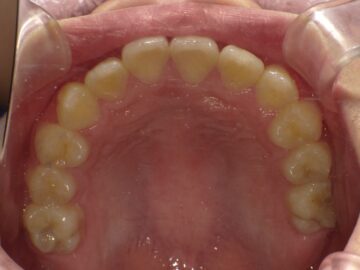

上顎の骨には繋ぎ目が存在しており、そこで左右二つの骨に分かれています。急速拡大装置を上顎に固定して装置の中央にあるネジを回すことで繋ぎ目を広げ、徐々に上顎の骨の変えていきます。そうすることで、顎の骨が正しい形に成長していくよう促され、永久歯を正しい位置で生えるように誘導できます。

上顎の拡大と下顎の歯の調整が進むと、機能的矯正装置であるアクチバトール(FKO)という装置を使用します。アクチバトール(FKO)は着脱式の矯正装置で、下顎を適切な位置へ誘導します。 顎の位置、形態が改善し、舌、口唇の位置、使い方が改善すれば、自然に歯の位置が変わって歯が綺麗に並ぶようになります。